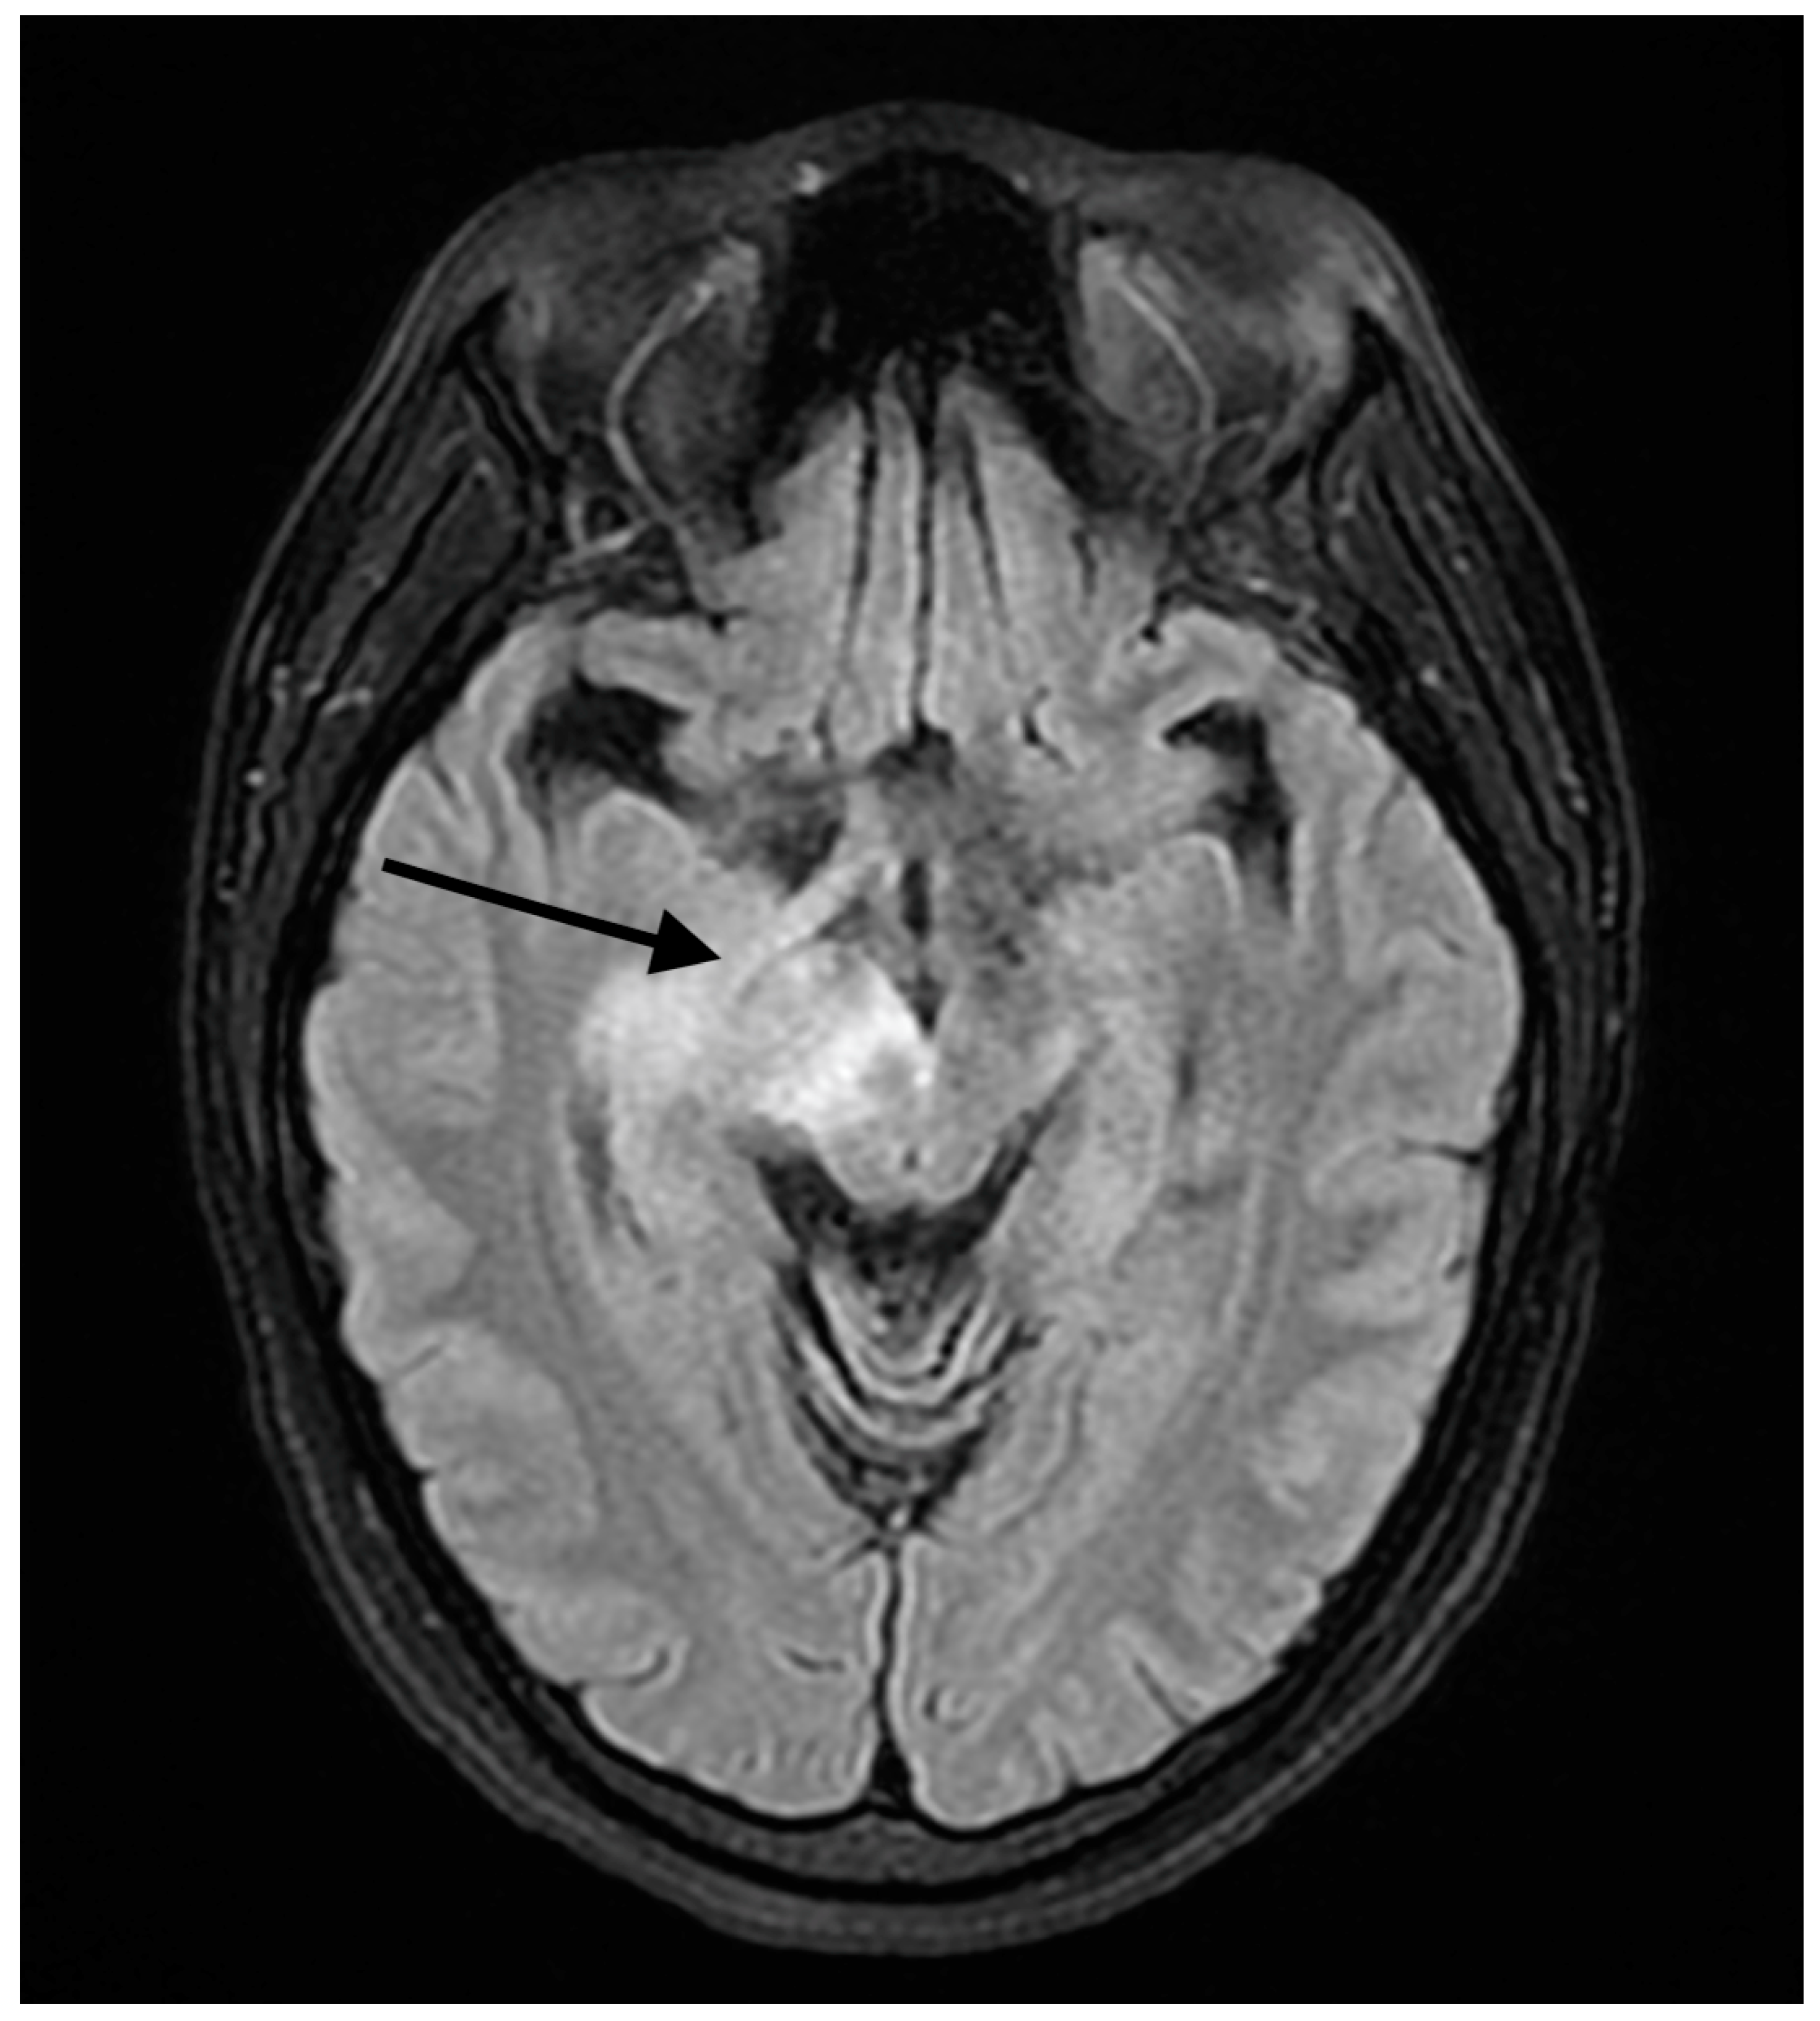

2. Detailed Case Description